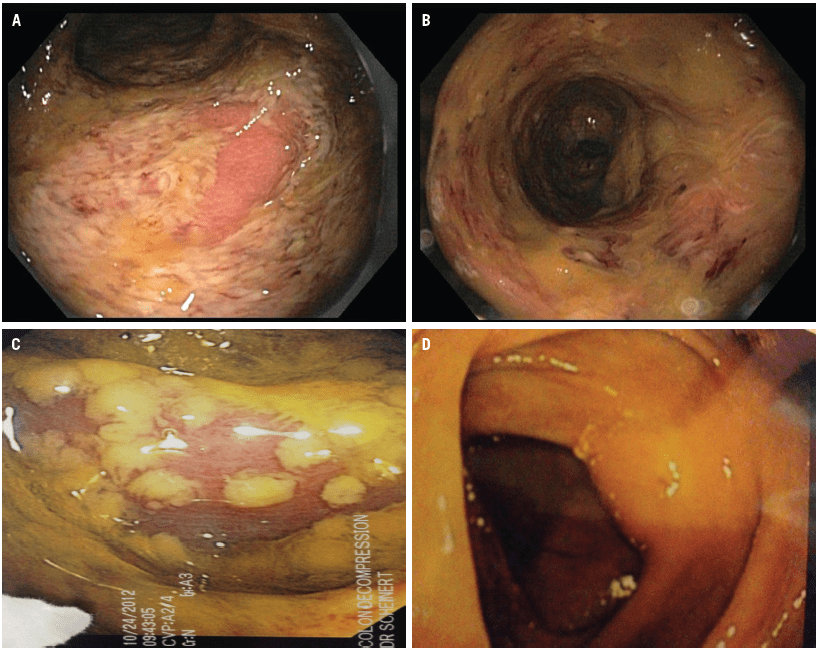

Difficileinfection is characterized by a wide range of symptoms, from mild or moderate diarrhea to severe disease with pseudomembranous colitis, colonic ileus, toxic megacolon, sepsis, or death. Diff is a germ (bacterium) that causes severe diarrhea and colitis (an inflammation of the colon). What does c diff diarrhea look like? Many infants are colonized by toxigenic or nontoxigenic c. C.